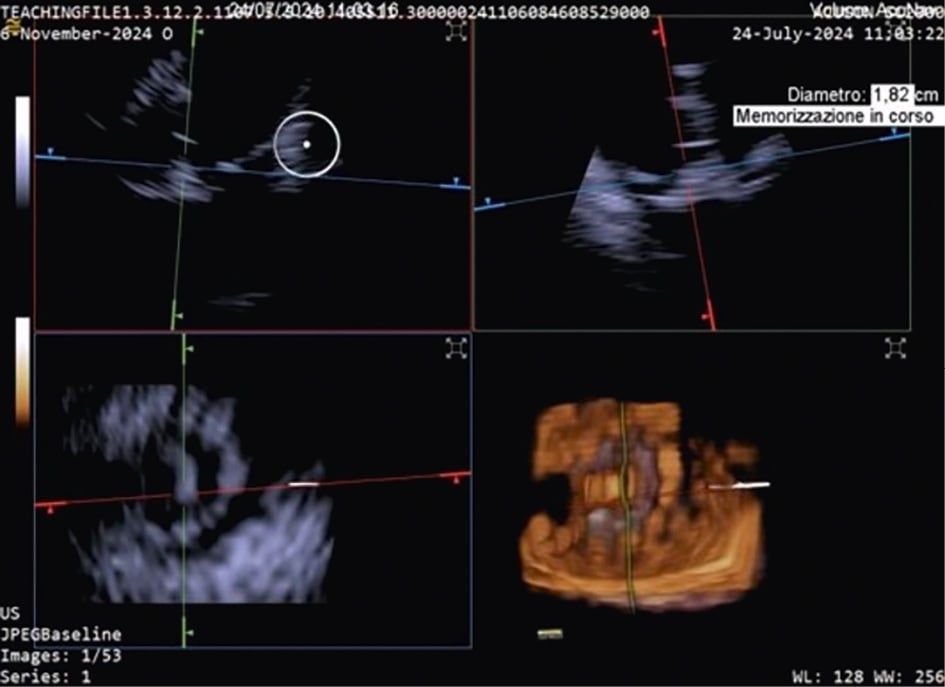

TTVR is a new technology used for tricuspid regurgitation (TR) treatment in patients not eligible for other percutaneous approaches23. The suitability for this treatment mainly depends on the annular dimensions, and unlike other treatment approaches, the imaging quality requirements are not very strict24. Three-dimensional ICE plays a crucial role in guiding the TTVR procedure, especially when TOE imaging is technically challenging. There are currently some cases described in the literature in which TTVR procedures are performed using combined 3D TOE-ICE imaging. Furthermore, there are only a limited number of centres with experience in ICE-guided TTVR24, but considering the advantages of image quality, it could become the standard in the coming years. Typically, the ICE probe is inserted via transfemoral or transjugular access and positioned in the middle of the RA. By placing the 3D ICE probe directly in the RA, the problem of acoustic interference can be overcome. Furthermore, this position allows for stable visualisation of the TV and enables the acquisition of a 3D MPR by placing the region of interest over the TV annulus, creating a 3D en face view. The leaflet capture and the valve implantation can be guided stepwise with 3D MPR25. A dedicated echocardiographer is essential to create and optimise the imaging modalities (TOE and ICE). In fact, considering that intraprocedural echocardiographic guidance is essential for procedural success, the interventional imager plays a crucial role in guiding the implantation of the device. Figure 5, Figure 6 and Moving image 8 show a Cardiovalve case (Venus Medtech) and a LuX-Valve case (Jenscare Scientific).

Figure 6. Three-dimensional MPR views of the tricuspid valve after LuX-Valve deployment. The atrial en face view allows the evaluation of possible residual leakage. MPR: multiplanar reconstruction